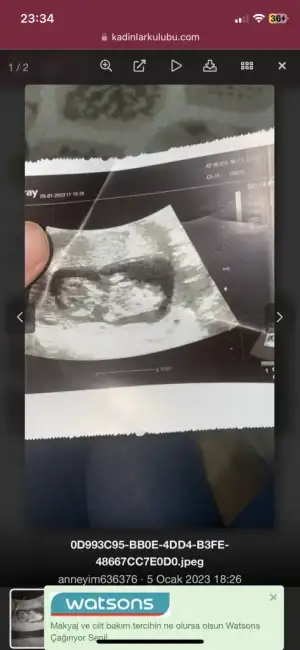

Cinsiyet tahmini

- cinsiyet tahmini 12 hafta

Tek bu mu var. Varsa başka atar mısınArkadaşlar merak işte 12 haftalık cinsiyet tahmini yapabilirmisiniz doktor bişi söylemedi.:)

Başka yok eskiler var 10 haftalıkken 9 haftalıkken varTek bu mu var. Varsa başka atar mısın

Bunlarda 10 haftalıkkenTek bu mu var. Varsa başka atar mısın

Erkek sankiArkadaşlar merak işte 12 haftalık cinsiyet tahmini yapabilirmisiniz doktor bişi söylemedi.:)

Erkek gibi hissettimBunlarda 10 haftalıkken

12 haftalık kendi ultrasonuma baktım benzemiyor. Benimki kız. Düz bir çıkıntı oluyor kızda. Erkekte daha küt yukarıya doğru bir çıkıntı oluyor. Nub teorisi yazıp bakabilirsinizİnşallah hissettiğiniz gibidir

Kızımın ultrasyonu var bu aylarda aynı bi farkı yok doktoru zorladım oda bana görmüyorum şuan bacak arasını ama kemik yapısına göre bazen tahmin yapabiliriz cok istediğiniz için söylüyorum kemik yapısına göre kız gibi demişti daha kesin bilgi vermedi yinede hayırlısı sağlıklı olsun kızıma bacı olsun allah hayırlısını versin herkese12 haftalık kendi ultrasonuma baktım benzemiyor. Benimki kız. Düz bir çıkıntı oluyor kızda. Erkekte daha küt yukarıya doğru bir çıkıntı oluyor. Nub teorisi yazıp bakabilirsiniz

Sırtı dönük benimkide böyle 2 haftadırArkadaşlar merak işte 12 haftalık cinsiyet tahmini yapabilirmisiniz doktor bişi söylemedi.:)

Merhaba bunlarda benden 12 artı 2 belli eder miliErkek gibi hissettim

Net değil pek. Anlayamadım maleseffMerhaba bunlarda benden 12 artı 2 belli eder mili